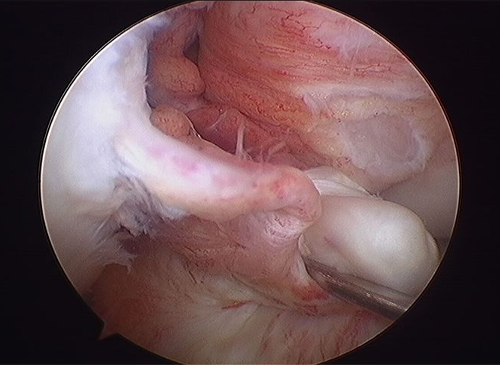

Before

-

-

After

- 최소 절개로 대퇴골과 경골의 병변 부위에 구멍을 내줍니다.

- 터널 구멍을 이용해 이식건을 통과시켜 넣습니다.

- 삽입된 인대를 당긴 후 양측에서 고정하여 새로운 인대 조직이 원래의 인대 강도를 유지하도록 잡아줍니다.